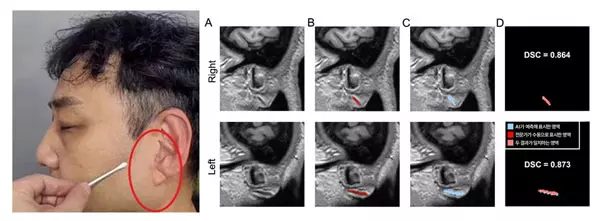

그간 프랭크 징후 구별 시 연구자가 실제 귀나 2차원 사진을 육안으로 관찰하는 방식에 의존해 주관적 요소가 개입될 수밖에 없었다. 이를 해결하고자 김기웅 교수팀(제1저자 서울대 융합과학기술대학원 조성만 연구원)은 3D 뇌 MRI에 양쪽 귓불을 포함한 얼굴이 함께 촬영된다는 점에 착안, 뇌 MRI에서 추출한 3차원 얼굴 이미지를 활용해 프랭크 징후를 자동으로 탐지하는 AI 모델을 개발했다. 분당서울대병원에서 수집한 400건의 뇌 MRI를 바탕으로 전문가가 수동으로 구분하고 표시한 프랭크 징후를 AI에 학습시켰다. 이후 학습에 사용하지 않은 별도의 분당서울대병원 데이터셋(총 600건)으로 1차 검증, 충남대병원·강원대병원·세브란스병원 다기관 데이터셋(총 460건)으로 2차 검증을 진행했다. 검증 과정에서는 전문가가 수동 표시한 프랭크 징후 영역과 AI가 자동으로 분할한 영역을 비교해 AI의 정확도를 평가했다. 여기서 ‘분할(segmentation)’이란 색칠 공부할 때 특정 부분만 색을 칠하듯이, AI가 귓불 주름을 찾아 표시하는 작업을 의미한다.

그 결과, 전문가가 수동으로 표시한 영역과 AI가 자동으로 분할한 영역의 일치 정도를 측정하는 DSC(Dice 유사도 계수, 1에 가까울수록 유사) 값이 두 차례의 검증에서 0.734, 0.714로 나타났다. 이는 AI가 찾아낸 영역이 전문가의 판단과 70% 이상 부합한다는 뜻으로, 의료영상 분야에서 높은 수준으로 인정받는다. 또한, 프랭크 징후의 유무를 얼마나 정확히 구분하는지 나타내는 AUC(분류 성능, 1에 가까울수록 우수) 값은 모두 0.9 이상을 기록, AI 모델이 다양한 임상 현장에서 안정적으로 작동할 수 있음이 입증됐다.